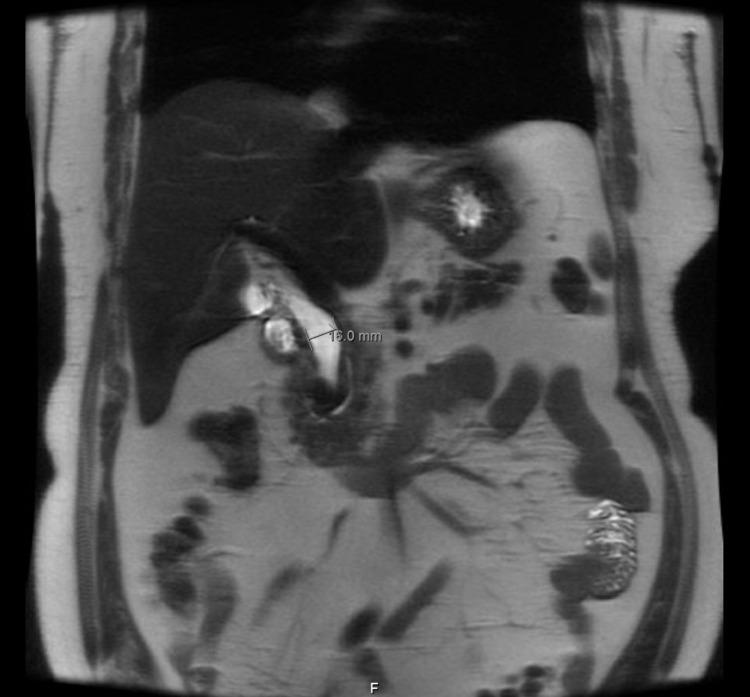

Lemmel syndrome is a rare cholestatic disease caused by a periampullary duodenal diverticulum (PAD) compressing the common bile duct (CBD) or pancreatic duct, which results in acute abdominal pain and/or obstructive jaundice in the absence of other pathology explaining the symptoms. It can be easily misdiagnosed unless carefully detected by abdominal ultrasound (US), barium studies, computed tomography (CT) scan, esophagogastroduodenoscopy (EGD), magnetic resonance cholangiopancreatography (MRCP), and endoscopic retrograde cholangiography (ERCP), which is also the treatment modality of choice. We herein report a case of a 62-year-old male presenting with prolonged hypochondrial pain. He was diagnosed with Lemmel syndrome after performing US, barium meal, CT scan, EGD, and MRCP that was managed successfully by ERCP with sphincterotomy and stent placement.

莱姆尔综合征是一种罕见的胆汁淤积性疾病,由壶腹周围十二指肠憩室(PAD)压迫胆总管(CBD)或胰管引起,在没有其他能解释症状的病理情况下,会导致急性腹痛和/或梗阻性黄疸。除非通过腹部超声(US)、钡剂造影、计算机断层扫描(CT)、食管胃十二指肠镜检查(EGD)、磁共振胰胆管造影(MRCP)和内镜逆行胰胆管造影(ERCP)仔细检测,否则很容易误诊,而ERCP也是首选的治疗方式。我们在此报告一例62岁男性,表现为长期季肋部疼痛。在进行了超声、钡餐、CT扫描、EGD和MRCP检查后,他被诊断为莱姆尔综合征,并通过ERCP行括约肌切开术和支架置入术成功治疗。